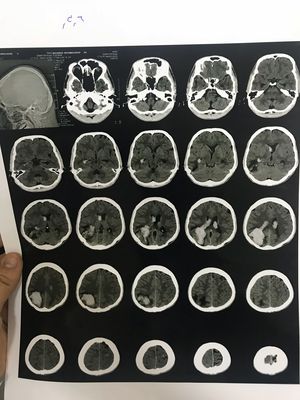

This CTscan belongs to a 19 years old motorcycle rider who had an accident 3weeks ago.

Hemorrhage in occipital lobe and temporal lobe??

Yup...looks like he has been having a slow bleed for the 3 weeks since the accident

We can see on the CTscan two zones where the brain has been affected:a little dot in the temporal lobe and a larger one in the occipital lobe...these two marks show Hemorrhage in those two lobes